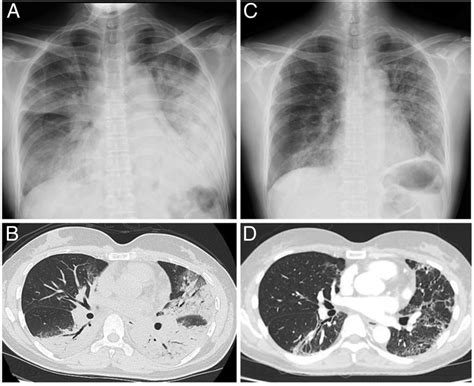

Diagnostic Procedures and Assessment

Identifying this condition in a clinical setting is usually done through direct observation and physical palpation. Emergency responders are trained to expose the patient’s chest fully to observe respiratory cycles. The following table highlights the difference between normal respiration and the signs observed during a flail chest event.

Monitoring for secondary complications is also vital during the weeks following the initial injury. Infections, such as pneumonia, are common in chest trauma patients because they struggle to cough and clear their lungs effectively due to the pain and instability. Regular follow-up imaging and pulmonary function tests are standard protocols to ensure that the healing process remains on track and that no long-term structural or functional deficits remain.